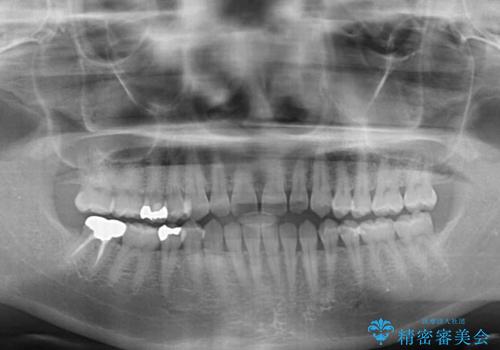

下の前歯が上の前歯を突き上げるように咬合するため、咬み合わせの位置を改善しながら隙間を閉じていきました。

元々の歯並びが悪くなかったため、9ヶ月で綺麗に仕上がりました。

すきっ歯は後戻りを起こしやすいため、上下ともに歯の裏側を細いワイヤーで固定した上で、リテーナーのマウスピースを装着していただいています。